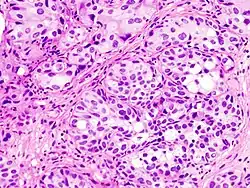

![]() Mikroskopisk billede af kræft udgået fra celler i blærevæggen. | |